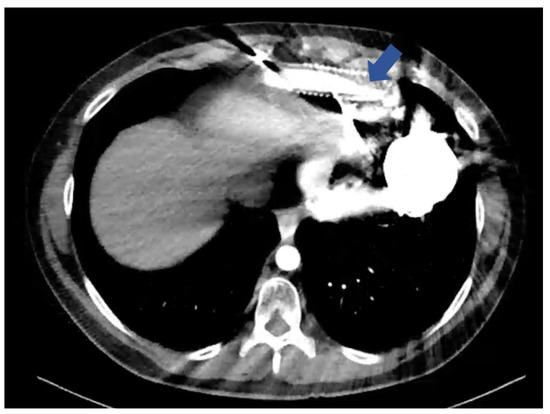

- eOGO diagnosis was confirmed through computed tomography (CT) imaging, percutaneous angiography (PA), or visualization during surgery.